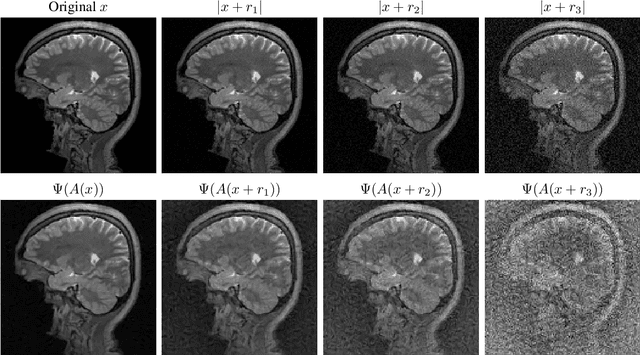

Abstract:There is overwhelming empirical evidence that Deep Learning (DL) leads to unstable methods in applications ranging from image classification and computer vision to voice recognition and automated diagnosis in medicine. Recently, a similar instability phenomenon has been discovered when DL is used to solve certain problems in computational science, namely, inverse problems in imaging. In this paper we present a comprehensive mathematical analysis explaining the many facets of the instability phenomenon in DL for inverse problems. Our main results not only explain why this phenomenon occurs, they also shed light as to why finding a cure for instabilities is so difficult in practice. Additionally, these theorems show that instabilities are typically not rare events - rather, they can occur even when the measurements are subject to completely random noise - and consequently how easy it can be to destablise certain trained neural networks. We also examine the delicate balance between reconstruction performance and stability, and in particular, how DL methods may outperform state-of-the-art sparse regularization methods, but at the cost of instability. Finally, we demonstrate a counterintuitive phenomenon: training a neural network may generically not yield an optimal reconstruction method for an inverse problem.

Abstract:Deep learning, due to its unprecedented success in tasks such as image classification, has emerged as a new tool in image reconstruction with potential to change the field. In this paper we demonstrate a crucial phenomenon: deep learning typically yields unstablemethods for image reconstruction. The instabilities usually occur in several forms: (1) tiny, almost undetectable perturbations, both in the image and sampling domain, may result in severe artefacts in the reconstruction, (2) a small structural change, for example a tumour, may not be captured in the reconstructed image and (3) (a counterintuitive type of instability) more samples may yield poorer performance. Our new stability test with algorithms and easy to use software detects the instability phenomena. The test is aimed at researchers to test their networks for instabilities and for government agencies, such as the Food and Drug Administration (FDA), to secure safe use of deep learning methods.